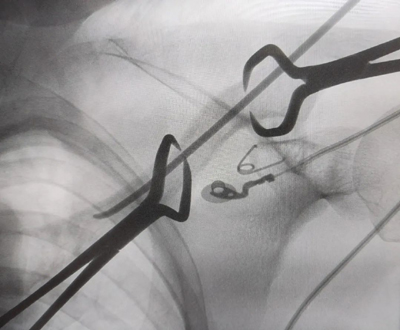

▲闭合复位下弹性髓内钉穿过骨折端

▲术中透视显示复位良好,固定可靠,弹性髓内钉置入最佳位置